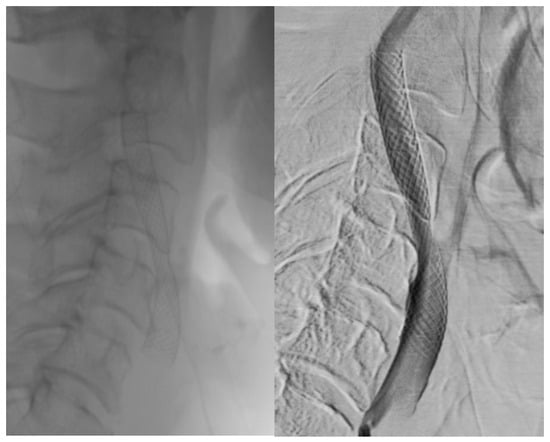

Visual differences between single- and double-layer carotid stents as seen during the angiography procedure are illustrated in Figure 2, Figure 3 and Figure 4.

Figure 2. Double-layer micromesh stent (Roadsaver-Terumo Interventional Systems).

Jcm 14 00888 g002